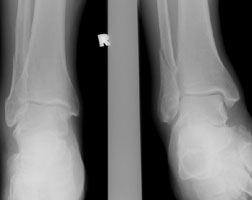

Weber C Fracture |

The Weber classification is used to determine the severity of tibiofibular ligament injury by the level of fibular fracture. The Weber C fracture consists of a proximal fracture of the fibula and a transverse fracture of the medial malleolus (or an intact malleolus and a ruptured deltoid ligament). This results in complete disruption of the tibiofibular ligament complex and is from pronation-lateral rotation injury.